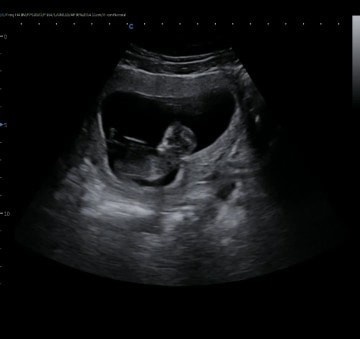

Usia kehamilan 14w4d

Bunda bunda bantu sharing ,apakah diusia 14w perut memang belum terlihat membesar dan keras ? Dan aku sedih bgt berat badan ku blm naik naik , Tp alhamdulillah di usg babynya sehat #seriusnanya

kalo saya yang penting janinnya sehat bun. saya sebelum hamil BB nya hanya 39kg bun. sekarang usia 18w1d BB 40 kg. awal mual muntah usia 8w-12w. mulai 13w sampai sekarang, alhamdulillah udah nikmat makan apapun. janin 14w masih kecil bun. perut baru sebesar itu. coba lihat digambar, 14w terletak diantara angka 12 dan 16.